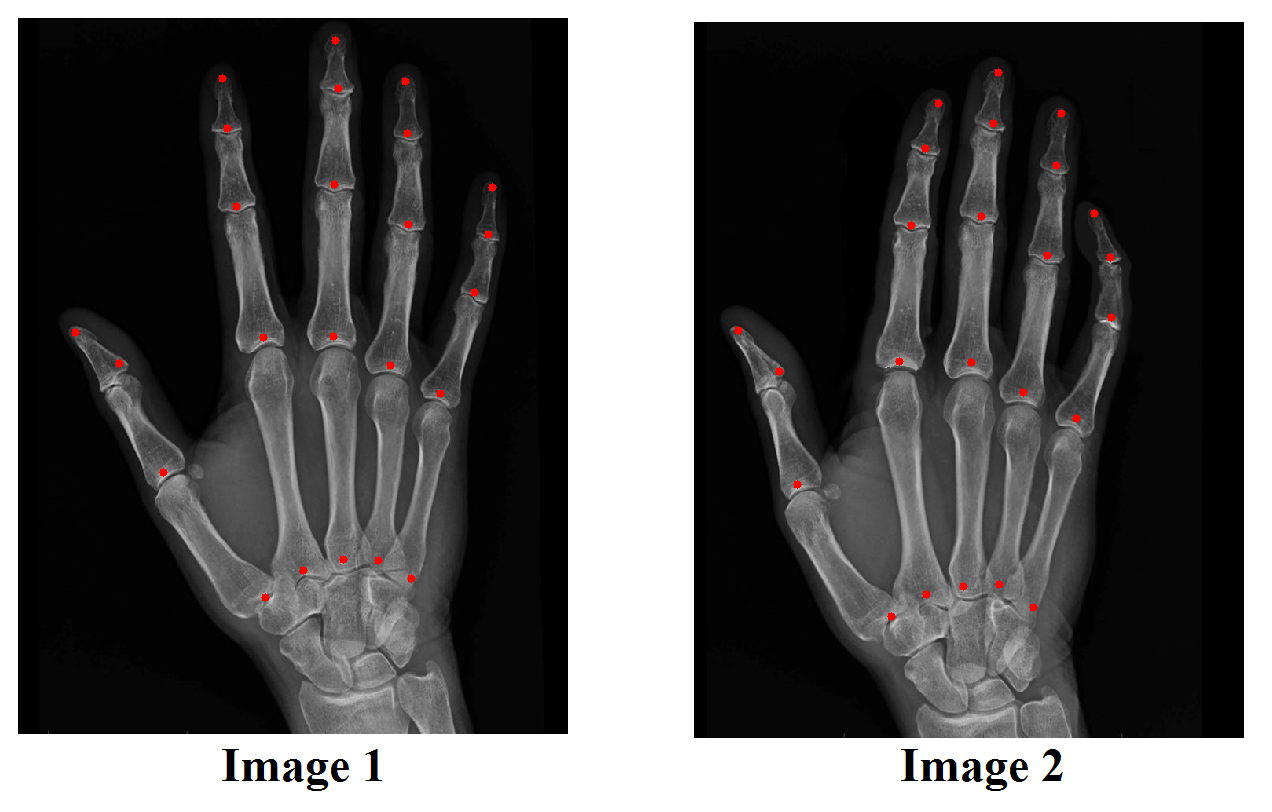

Example 7

We test the hybrid registration algorithm on real images. Figure 12 shows two images of the human hands. Corresponding landmark features are labeled on each images. In Figure 13, we show the registration results using different approaches. Figure 13(B) shows the deformed image from Image 1 using the landmark based registration model. Notice that if we only use landmarks as constraints to guide the registration, the deformed image is very different (see regions in the red boxes) from the target image (as shown in (A)). (C) shows the deformed image from Image 1 using the intensity based registration model. Similarly, the deformed image is very different (see regions in the red boxes) from the target image if only intensity information is used. (D) shows the deformed image from Image 1 using the proposed hybrid registration model. The deformed image closely resembles to the target image. In fact, the intensity mismatching error is less than 1%, meaning that the registration is very accurate.